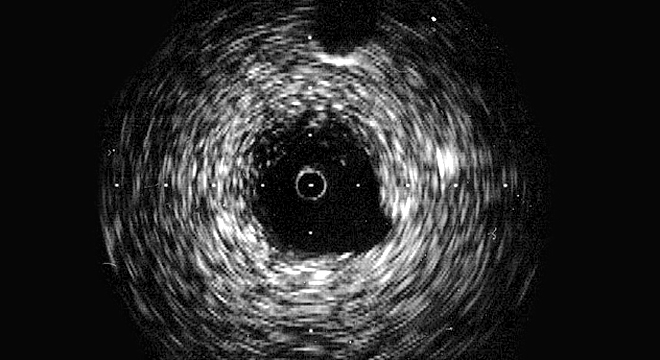

Arterienverkalkung (Arteriosklerose) ist eine langsam über Jahre fortschreitende Veränderung der arteriellen  Blutgefässe, bei der sich unter anderem Blutfette (Cholesterin), Kalk und Bindegewebe in den Gefässwänden ablagern. Diese Ablagerungen werden als Plaques bezeichnet. Die Gefässwände ''verkalken'', verlieren ihre Elastizität und der Gefässdurchmesser verengt sich zunehmend. Die Folge: Das Blut kann nicht mehr ungehindert fliessen bzw. kommt es zum kompletten Verschluss eines Gefässes.

• Spezieller Ultraschall (Dopplersonographie) zur Darstellung des Blutflusses in den arteriellen Blutgefässen

• Magnetresonanztomographie  (MR-Angiographie) oder Computertomographie (CT-Angiographie)